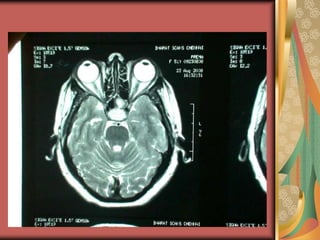

Chiasma

Lower nasal fibres cross low and

anteriorly

Upper nasal fibres cross high and

posteriorly

Macular fibres also cross in the

posterior part of the chiasm.

Location of chiasma

Central fixation -80%- above the sella

Pre fixed chiasm-10%-located anteriorly-

so pitutary tumour involves the optic tract

first [lower temporal fields first]

Post fixed chiasm-10%-located posteriorly-

so optic nerve gets involved first

[upper temporal fields first]